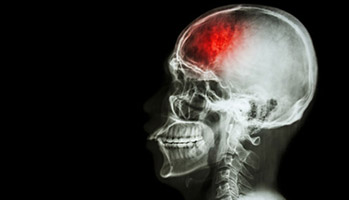

AVC ischémique : le duo clopidogrel-aspirine réduit le risque de récidive

L’association du clopidogrel à l’aspirine est un duo gagnant en cas d’AVC ischémique ou transitoire. Chez les patients ayant subi un accident vasculaire cérébral ischémique léger ou transitoire, le traitement combiné clopidogrel-aspirine initié dans les 72 heures suivant le début des symptômes réduit le risque de récidive à 90 jours par rapport à l'aspirine seule. En revanche, l’association est associée à un risque faible mais plus élevé d’hémorragie modérée à sévère. Ce travail est paru dans le NEJM. Un double traitement antiplaquettaire réduit le risque de récidive d'accident vasculaire cérébral par rapport à l'aspirine seule lorsque le traitement est initié tôt (≤ 24 heures) après un premier événement. Une équipe a évalué l'effet du clopidogrel et de l'aspirine par rapport à l'aspirine seule administrée dans les 72 heures suivant le début de l'ischémie cérébrale aiguë.